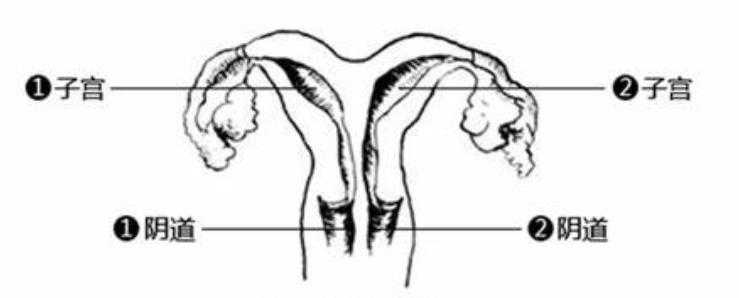

纵隔子宫夫妻生活是否会痛?

纵隔子宫属于先天性子宫发育畸形,通常对性生活无直接影响。但若伴有阴道纵隔,同房时可能会产生疼痛感。在辅助生殖术前检查中,若发现纵隔导致了反复流产或不孕,则需进行宫腔镜手术。若妇科阴道镜显示阴道同样存在发育畸形,可配合进行阴道整形手术,以改善生活质量及后续受孕条件。